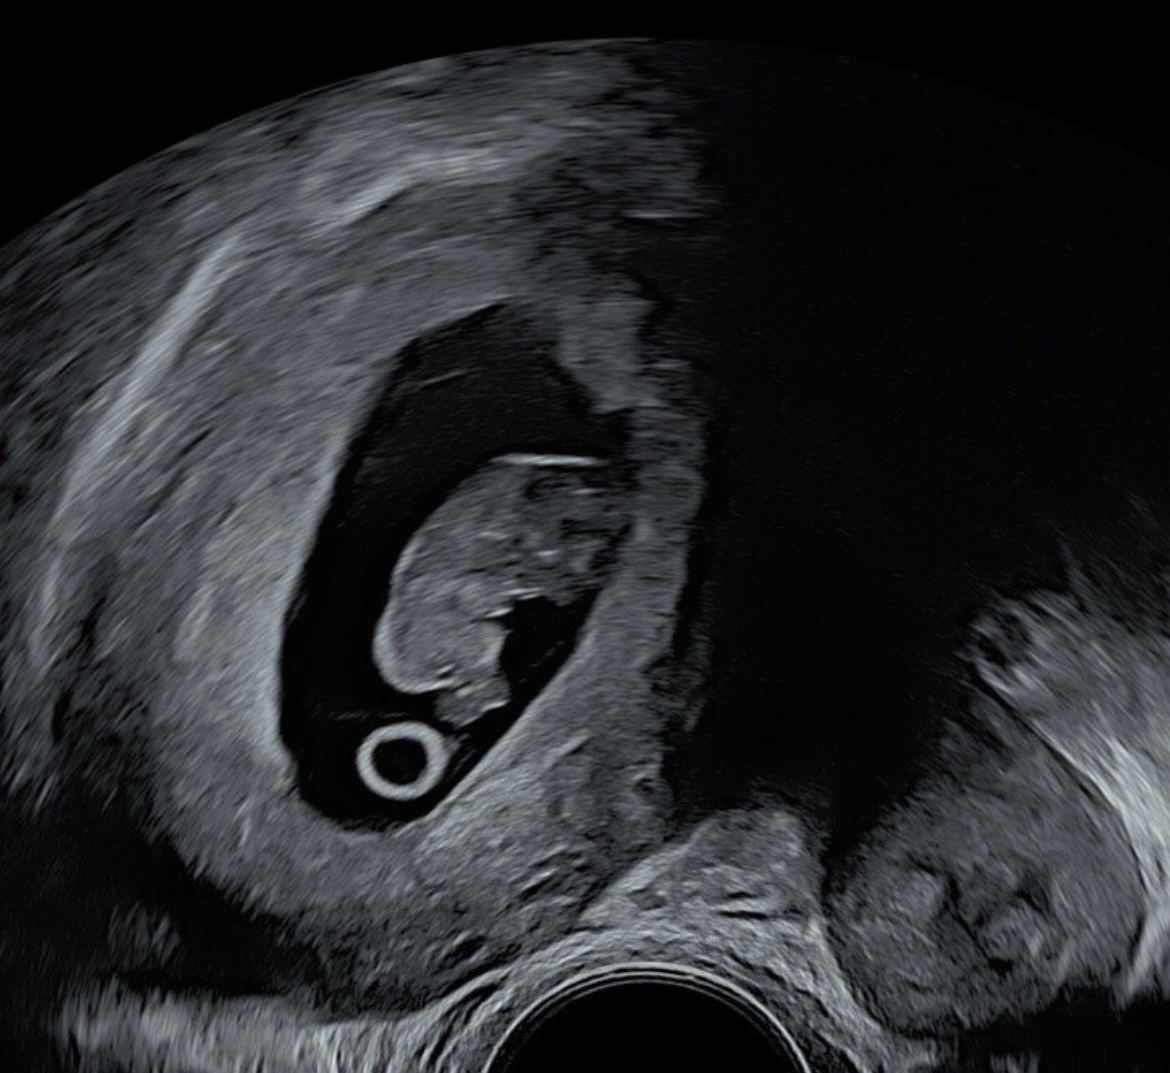

Lille bamsemumsen hadde vokst som den skulle og var 1,97cm lang, med sterke hjerteslag. Helt etter planenvi så to armer, to bein, en rygg og hode

Eneste bekymringen her er jo at den som sagt ligger litt høyt mot høyre, og dr. Lundring tok seg god tid. Han sjekket alt fra alle kanter, og konkluderte med at han trodde det skulle gå helt fint. Men for å være 100% sikker så må jeg inn på Ahus for å få flere øyer på saken. Men jeg stoler veldig på at Lundring at han kan dette godt.

Eneste bekymringen her er jo at den som sagt ligger litt høyt mot høyre, og dr. Lundring tok seg god tid. Han sjekket alt fra alle kanter, og konkluderte med at han trodde det skulle gå helt fint. Men for å være 100% sikker så må jeg inn på Ahus for å få flere øyer på saken. Men jeg stoler veldig på at Lundring kan dette godt.